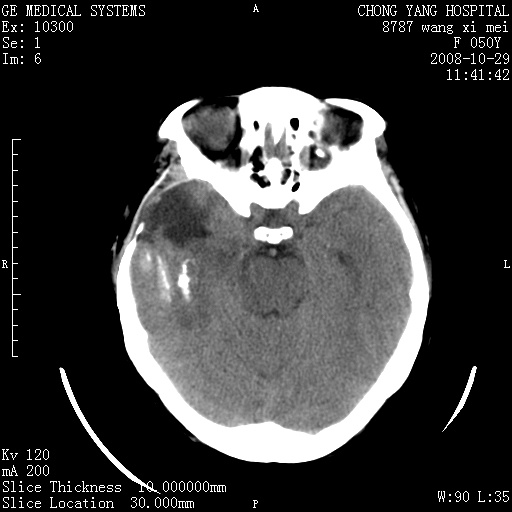

标题: CT16469:女,50岁,胶质瘤术后6年,今平扫加增强,请大家帮 [打印本页]

标题: CT16469:女,50岁,胶质瘤术后6年,今平扫加增强,请大家帮

右侧颞顶部可见低密度实变影,内见不规则钙化灶,边界不清,占位效应明显,侧脑室后角受压移位,符合胶质瘤术后复发改变。

右颞骨局限性缺如,局部脑组织无外隆。右颞叶可见片状脑脊液样低密度影,边缘较清,右侧侧脑室三角区可见一块状等密度影,且伴有强化,余未见明显异常改变。

考虑:右大脑术后改变伴肿瘤复发。

手术后局部片状低密度改变(软化灶),其后方颞叶似等密度病灶,界限不清,内见钙化,有轻度占位效应,但增强后强化之血管走行如常。应不考虑:复发!

应考虑肿瘤复发,右颞顶叶已出现轻度强化肿块.必要时可与原片比较以下.

右侧颞顶部混杂密度影,内有钙化,有占位效应。应该是复发灶。结合术后片更好。